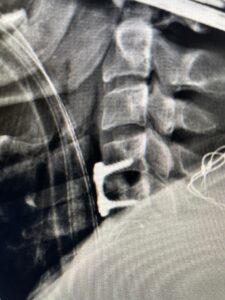

This 47-year-old male who four months prior was lifting weights developed sharp pain in his neck. After that he developed progressive numbness in his arms, neck pain and headache. He said that the right arm was worse than the left. On examination the patient had long tract weakness on the right side which included his triceps, finger extensors, hip flexors, and dorsiflexors. The patient did not have hyperreflexia. MRI (Fig. 2) demonstrated a massive, extruded disc herniation with severe cord compression. The patient because of progressive myelopathy and spinal cord compression was indicated for anterior cervical discectomy and fusion at C4-5 (Fig. 3). Patient had significant improvement of weakness and numbness post operatively.

Fig. 3 Intraoperative lateral cervical X-Ray demonstrating C4-5 ACDF

This 36-year-old female who had a long history of neck pain had a history on MRI of a C5-6 bulge. She recently after diving into a pool (not hitting her head on bottom) developed progressive problems with her arms. She had developed spontaneous shocks going down her arms and in the back of her neck. Spontaneous shocks going down the neck and spine is called a Lhermitte’s phenomenon and can occur with spinal cord compression and also with multiple sclerosis. On examination, the patient had long tract weakness of her arms, right greater than left. Her finger extensor weakness was profound on the right. MRI (Fig. 4) of the cervical spine revealed a massive C5-6-disc herniation causing significant cord compression right greater than left with subtle cord signal change. Because of the severe myelopathy, the patient was indicated for surgery. A C5-6 anterior cervical discectomy and fusion was performed (Fig. 5). The patient had a dramatic improvement of her strength in the recovery room.

Fig 5. Intraoperative Lateral Cervical X-Ray demonstrating C5-6 ACDF